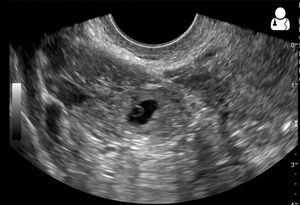

초음파 검사는 자궁외 임신 진단의 핵심적인 방법이다. 특히 질식 초음파 검사는 나팔관 내에 임신낭이 있고 태아 심장이 보이는 경우 자궁외 임신 진단에 매우 높은 특이성을 보인다. 이 검사는 질 내에 변환기를 삽입하여 진행하며[32], 자궁외 임신에 대해 최소 90%의 민감도를 가진다.[5]진단적 초음파 소견은 다음과 같다: